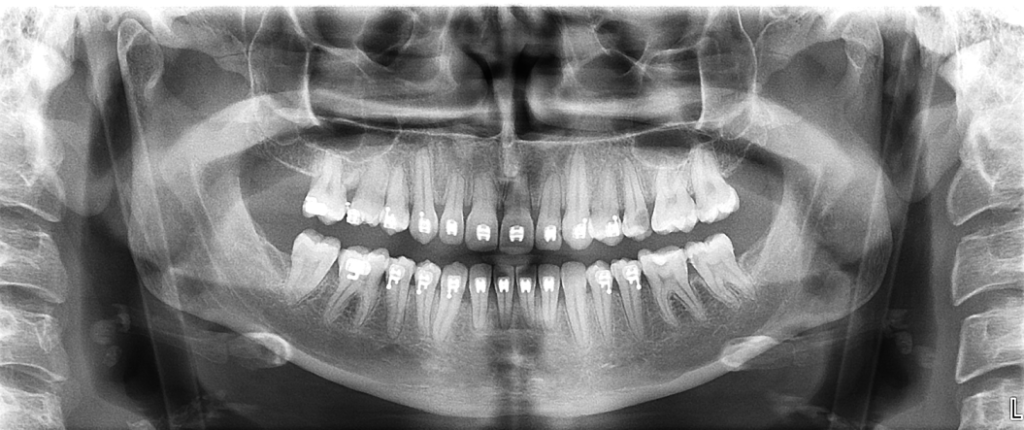

Importancia del correcto posicionamiento del paciente en la ortopantomografía

La ortopantomografía es una de las pruebas radiológicas más solicitadas en odontología. Sin embargo, su calidad depende en gran medida de la colaboración y del correcto posicionamiento del paciente, un factor clave para obtener una imagen diagnóstica fiable.

Durante la ortopantomografía, el equipo realiza un barrido alrededor de la cabeza del paciente. Si la posición no es correcta, pueden aparecer:

• Distorsiones de la imagen

• Dientes desenfocados o alargados

• Superposiciones óseas

• Pérdida de información diagnóstica

Estos errores pueden dificultar la interpretación clínica y, en algunos casos, obligar a repetir la prueba.